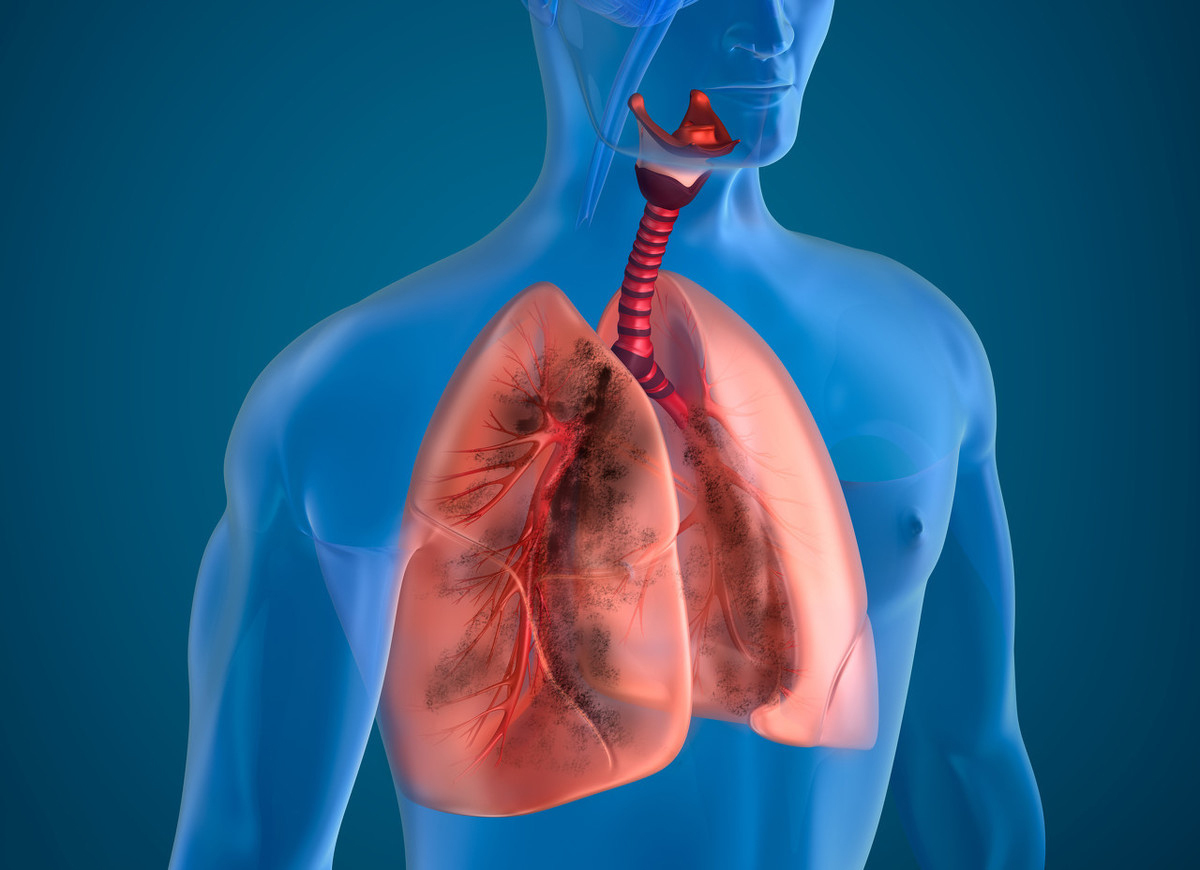

慢阻肺是一种严重危害人类健康的多发病,不仅会严重影响患者的生命质量,而且病死率较高,还会给患者及其家庭以及社会带来沉重的经济负担。慢阻肺,全称叫做慢性阻塞性肺疾病(COPD),是由于患者长期处于吸烟、空气污染、工作环境中而引起的肺功能损害,尤其是吸烟,至少95%的慢阻肺患者都有长期吸烟的习惯。

1、咳嗽:咳嗽是慢阻肺最早出现的临床症状,一开始为间断性咳嗽,早晨较重,以后早晚或整日均可有咳嗽,夜间咳嗽常不显著。少数患者无咳嗽症状,但肺功能显示明显气流受限。

2、咳痰:咳少量粘液性痰,清晨较多。合并感染时痰量增多,可有脓性痰。少数患者咳嗽不伴咳痰。

3、气短或呼吸困难:慢阻肺的典型表现,早期仅于活动后出现,后逐渐加重,严重时日常活动甚至休息时也感气短。

此外,长期肺功能下降可引发全身症状,部分患者特别是重度患者还可以出现食欲减退、体重下降、精神抑郁等症状。